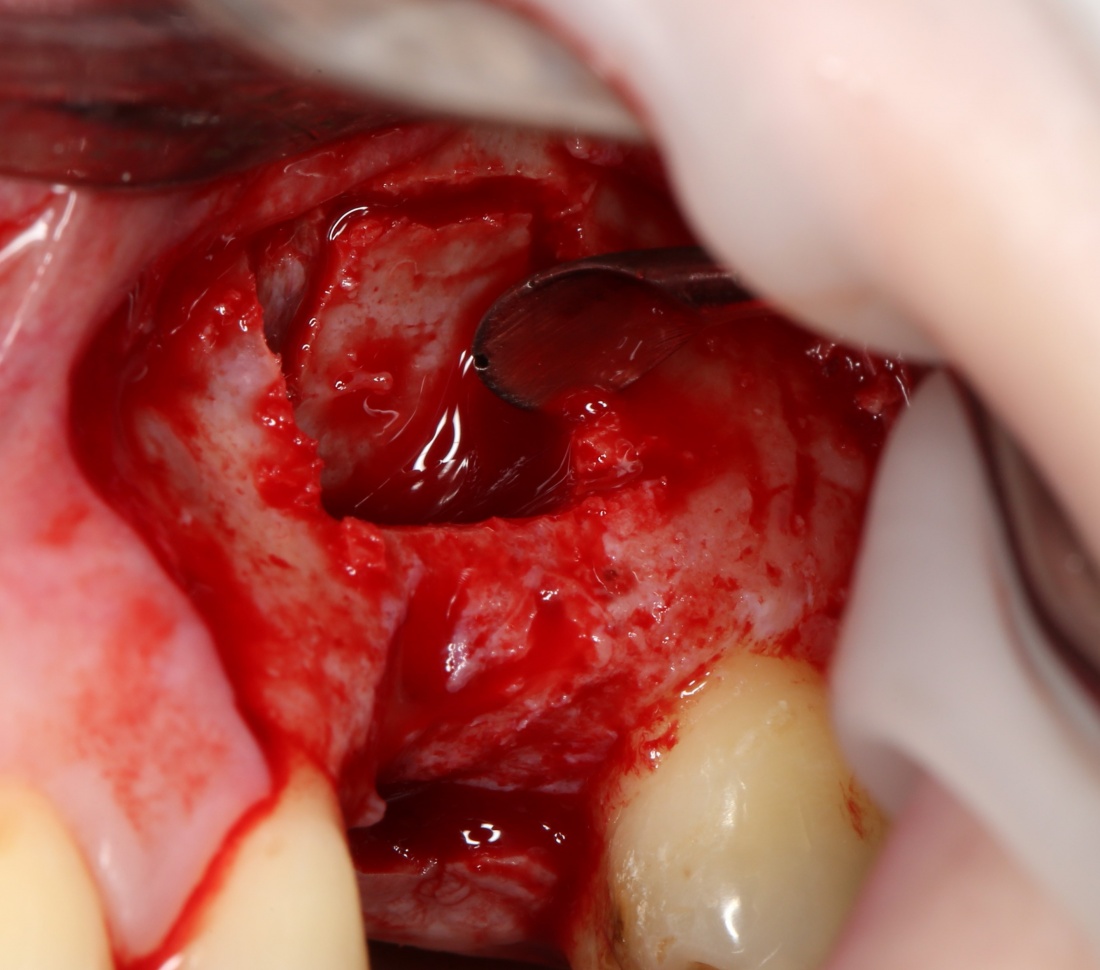

Простой синуслифтинг. Часть I.